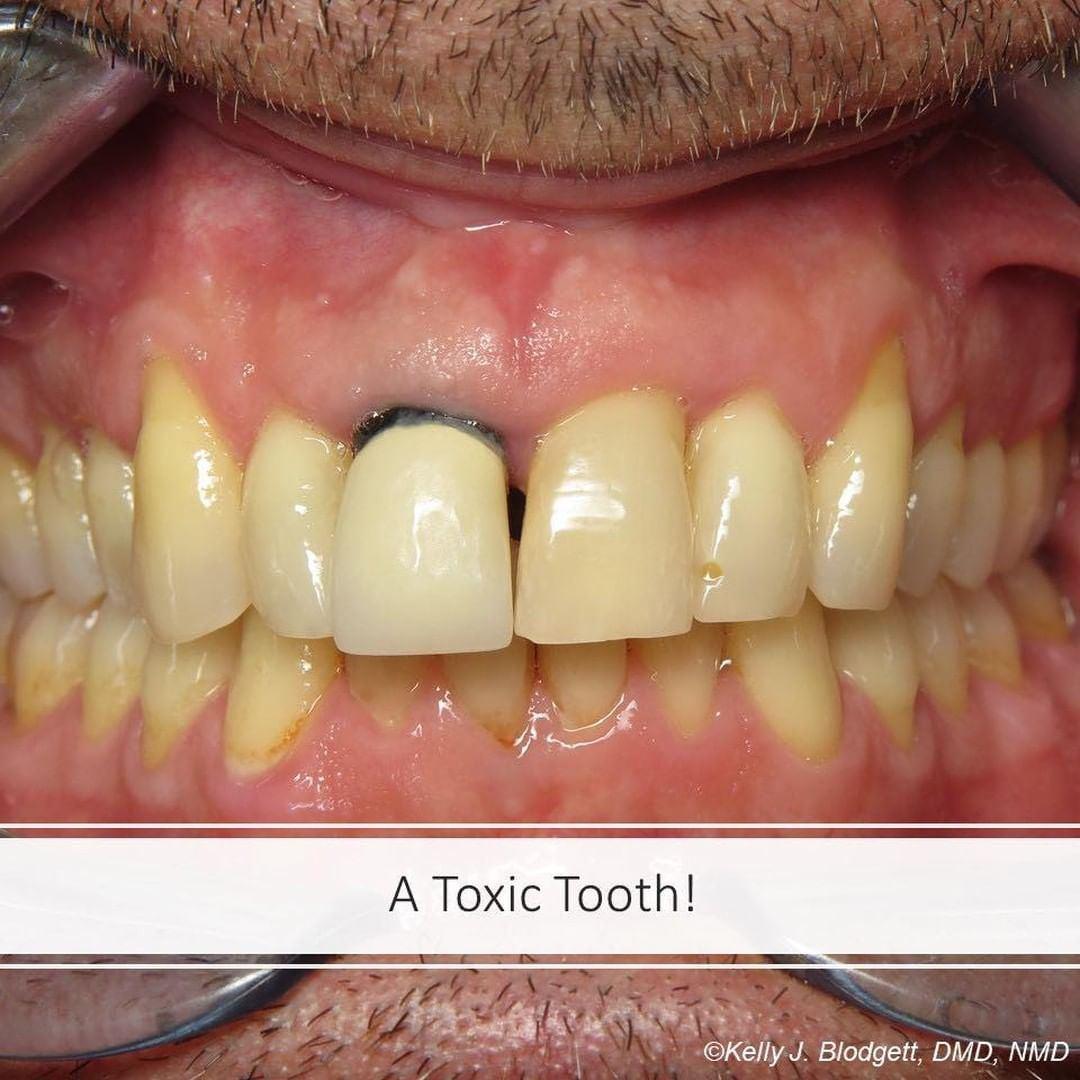

Toxic Tuesday: Gangrene tooth causing sinus and lung problems.

Today’s story is about a middle-aged man who injured his front tooth as a child. After the traumatic tooth accident, the nerve died and root canal therapy was performed. In his early 20s another tooth became painful in the upper right posterior jaw. His upper right first molar was also treated with a root canal. Within a few years he started experiencing chronic lung and sinus problems. He shared that he has suffered for more than a decade with not being able to breathe through his nose. He also shared that his nose runs and has drainage constantly. His throat experiences swelling and he can’t sleep well due to his limited breathing capacity.

As it turns out, both of the teeth in which he had root canal therapy were suffering from severe infection and the upper right molar is on the energetic meridian of the lungs and sinuses! The two teeth were extracted following the BDC protocol and the sockets were grafted with his own healing cells which we refer to as “L-PRF” (a concentration of his own immune cells and clotting factors). A fake porcelain tooth was created using the “CEREC” system in about 20 minutes and then glued to the adjacent teeth. Within a couple months his lung and sinus issues resolved.